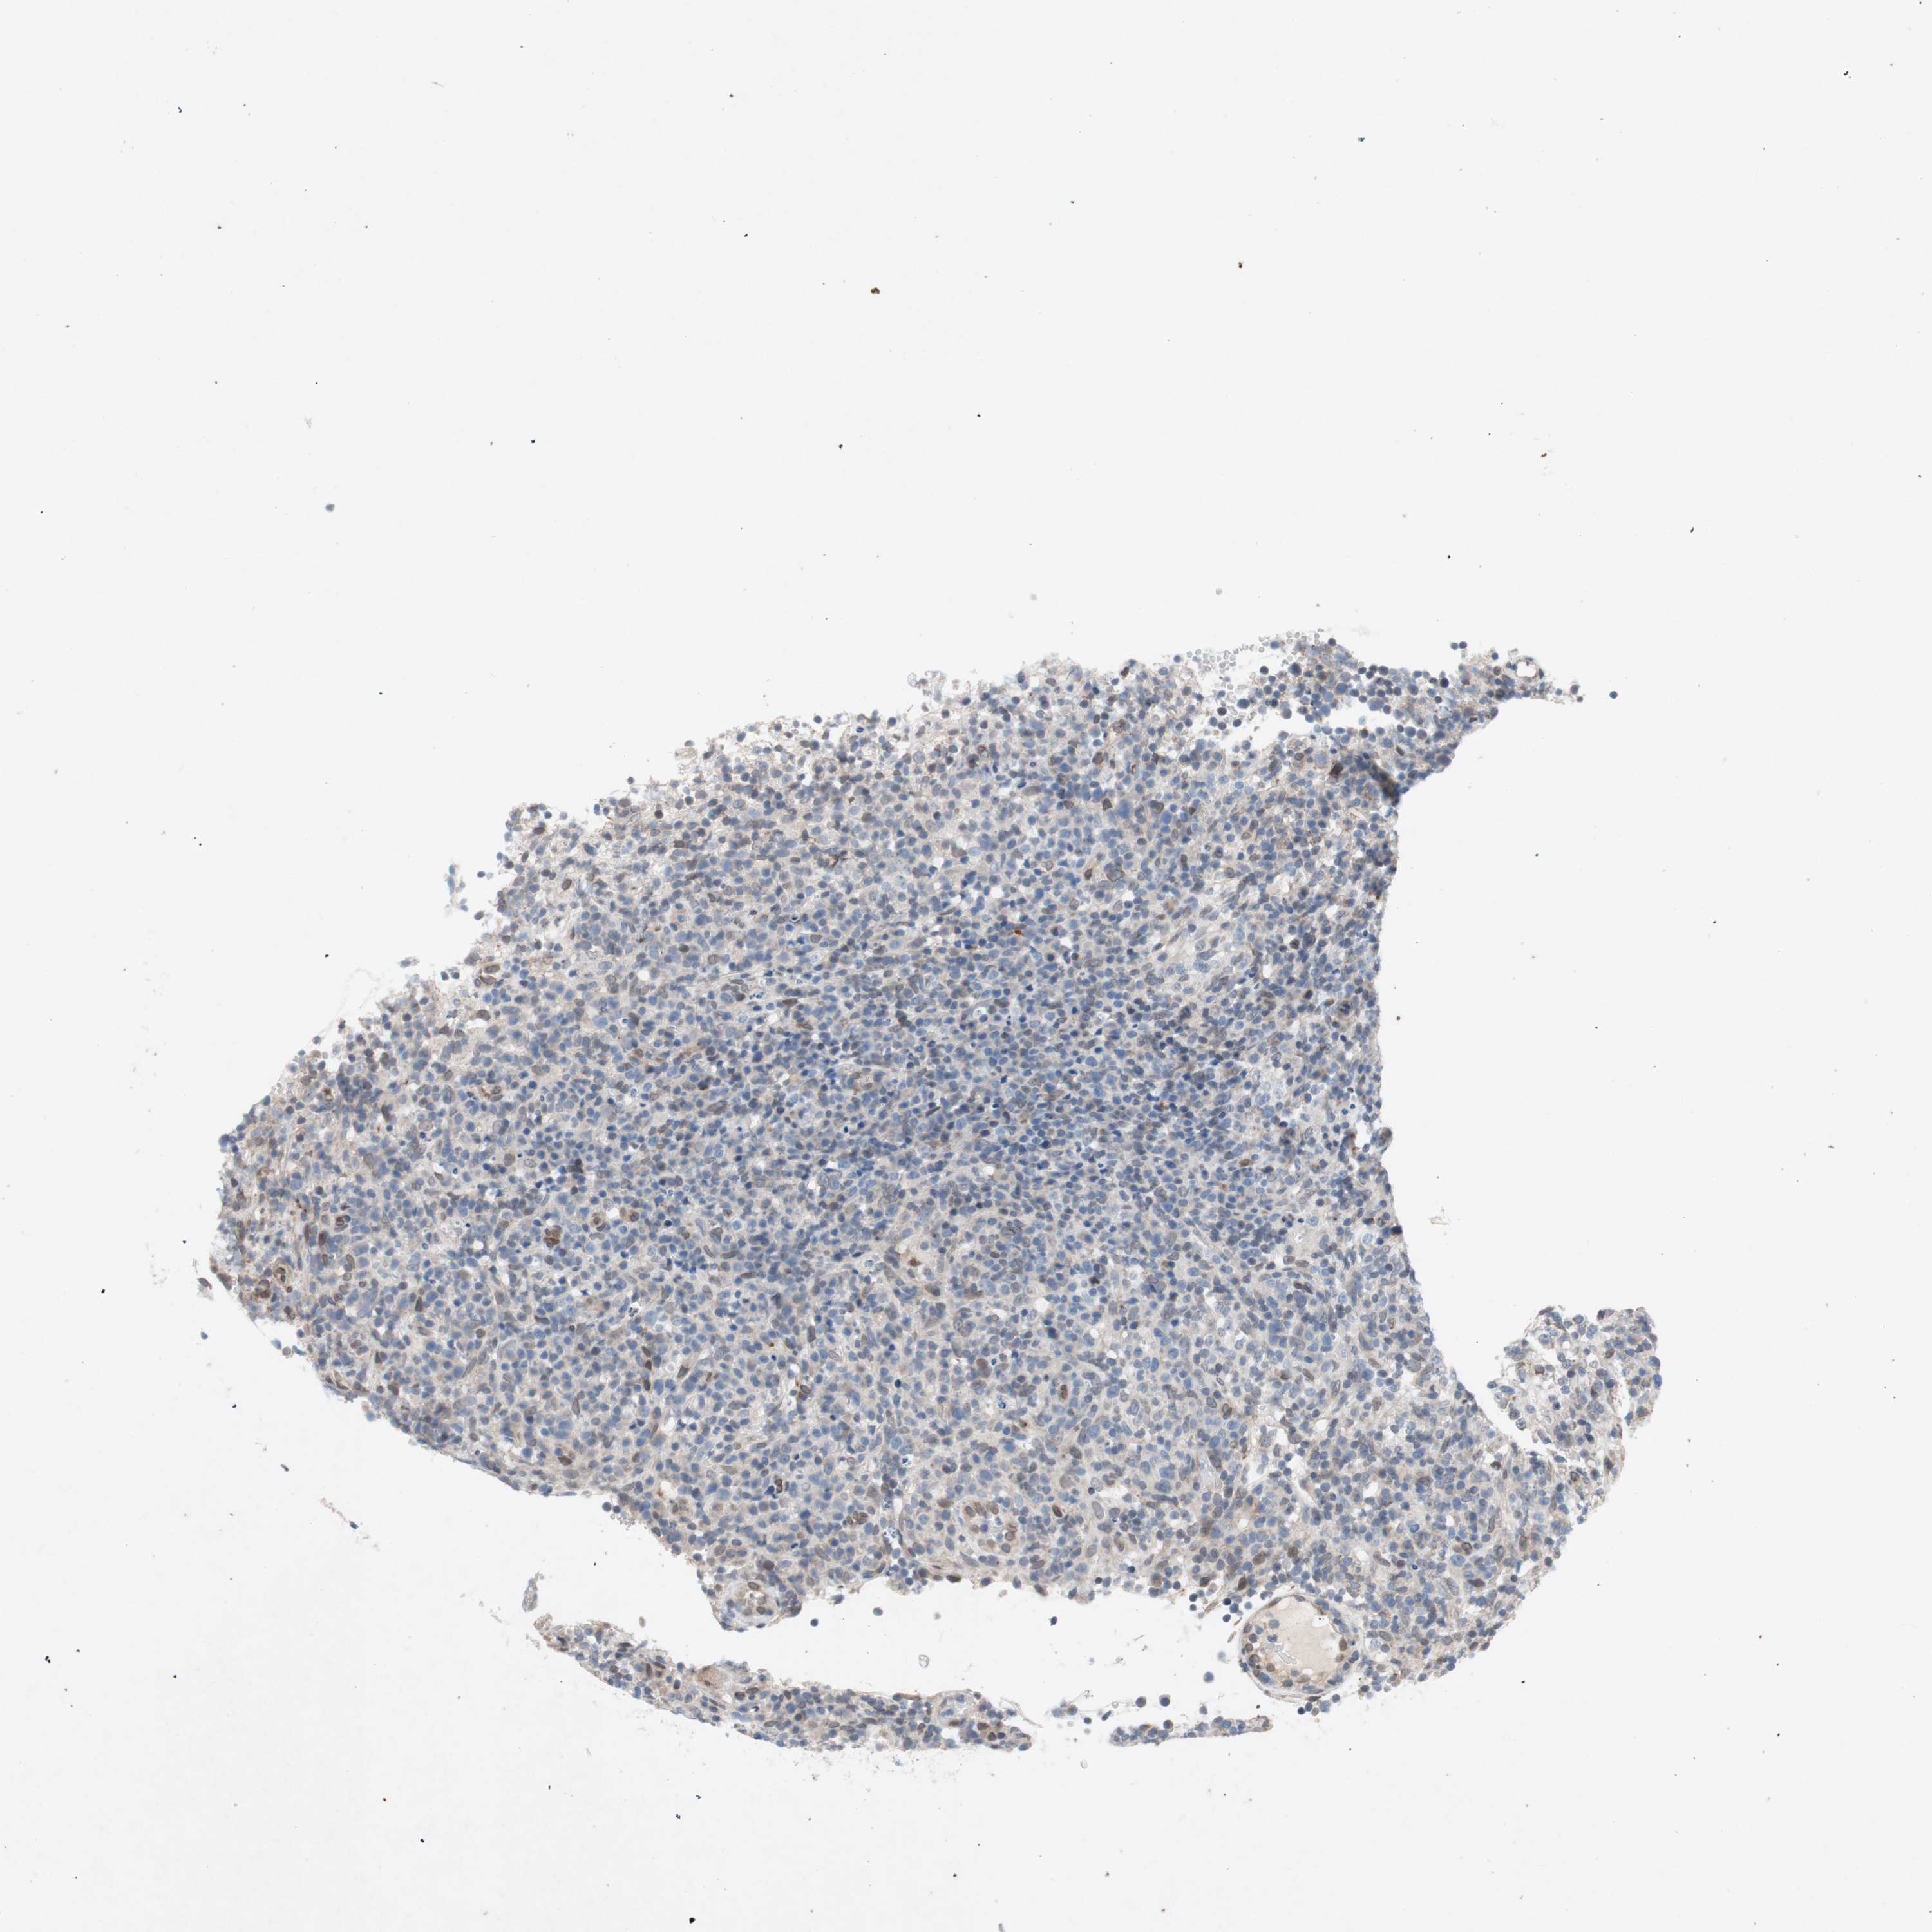

CANCER LYMPHOMA Show tissue menu

LYMPHOMA - Protein expressioni

A mouse-over function shows sample information and annotation data. Click on an image to view it in a full screen mode. Samples can be filtered based on level of antibody staining by selecting one or several of the following categories: high, medium, low and not detected. The assay and annotation is described here.

Each image is clickable and will lead to virtual microscopy that enables deeper exploration of all samples and also displays staining intensity scores, fraction scores and subcellular localization as well as patient and tissue information for each sample.

Antibody HPA001056

Malignant lymphoma, non-Hodgkin's type, High grade

Hodgkin's disease, NOS

Malignant lymphoma, non-Hodgkin's type, Low grade